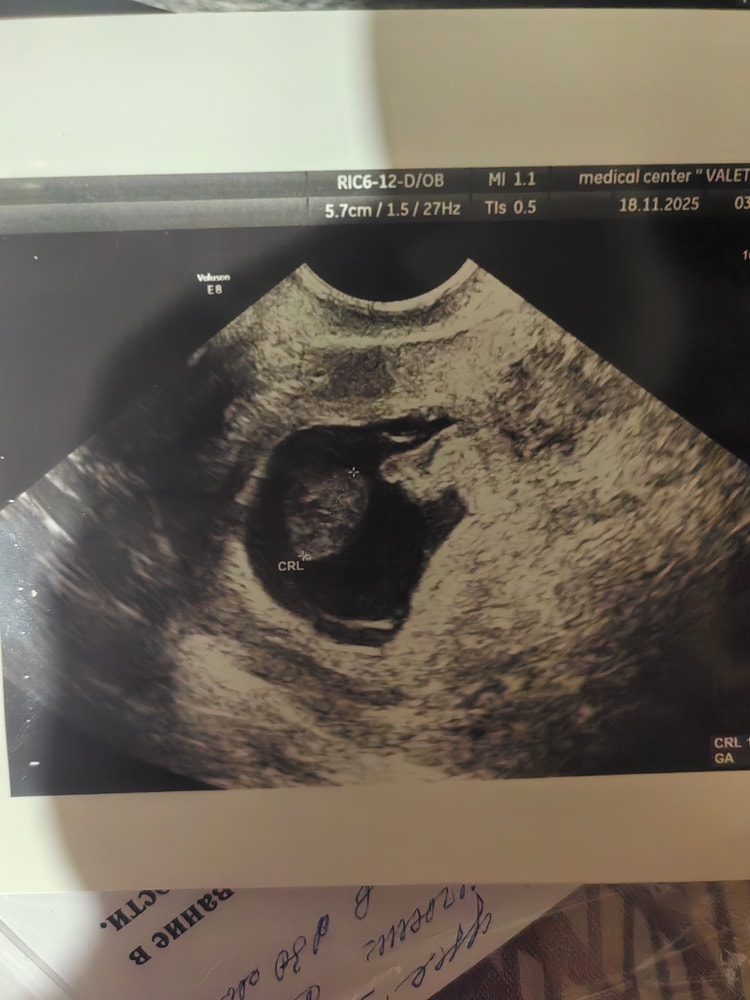

Galina, да( Светлана права … Когда тонус оно сплющено . Я сейчас вам покажу какое у меня было вначале .. К меня был тонус . А у вас как звездочкой , без четкого контура . Да , к сожалению такое бывает . И по статистике , у каждой женщины 1-2 зб и подобных поломок является нормой , если это не на постоянной основе с каждой беременностью .

У меня замер на 7+1 тоже яйцо как клякса .